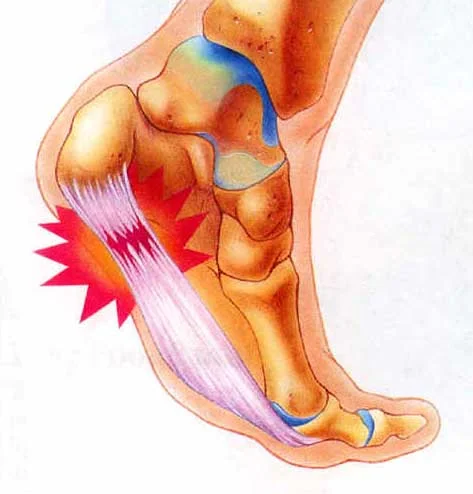

Fascitis plantar

Ejercicios para la fascitis plantar